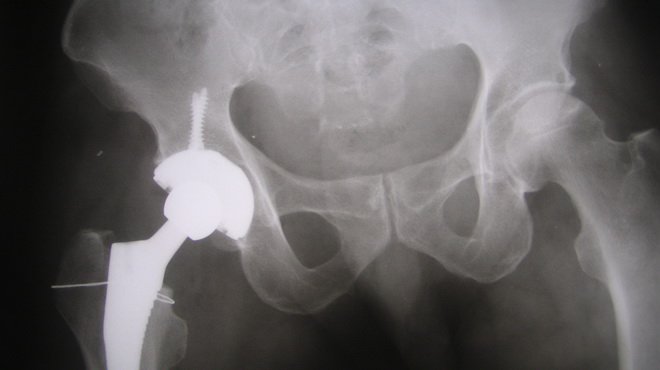

- X-quang: X-quang có thể phát hiện được hoại tử vô khuẩn chỏm xương đùi ở giai đoạn muộn. Các hình ảnh thường thấy là xẹp chỏm từ mức độ nhẹ đến nặng, nặng nhất chỏm bị tiêu một phần hoặc hoàn toàn, hẹp khe khớp. Ngoài ra có những biến đổi cấu trúc xương như mất chất khoáng khư trú, vỡ xương dưới sụn